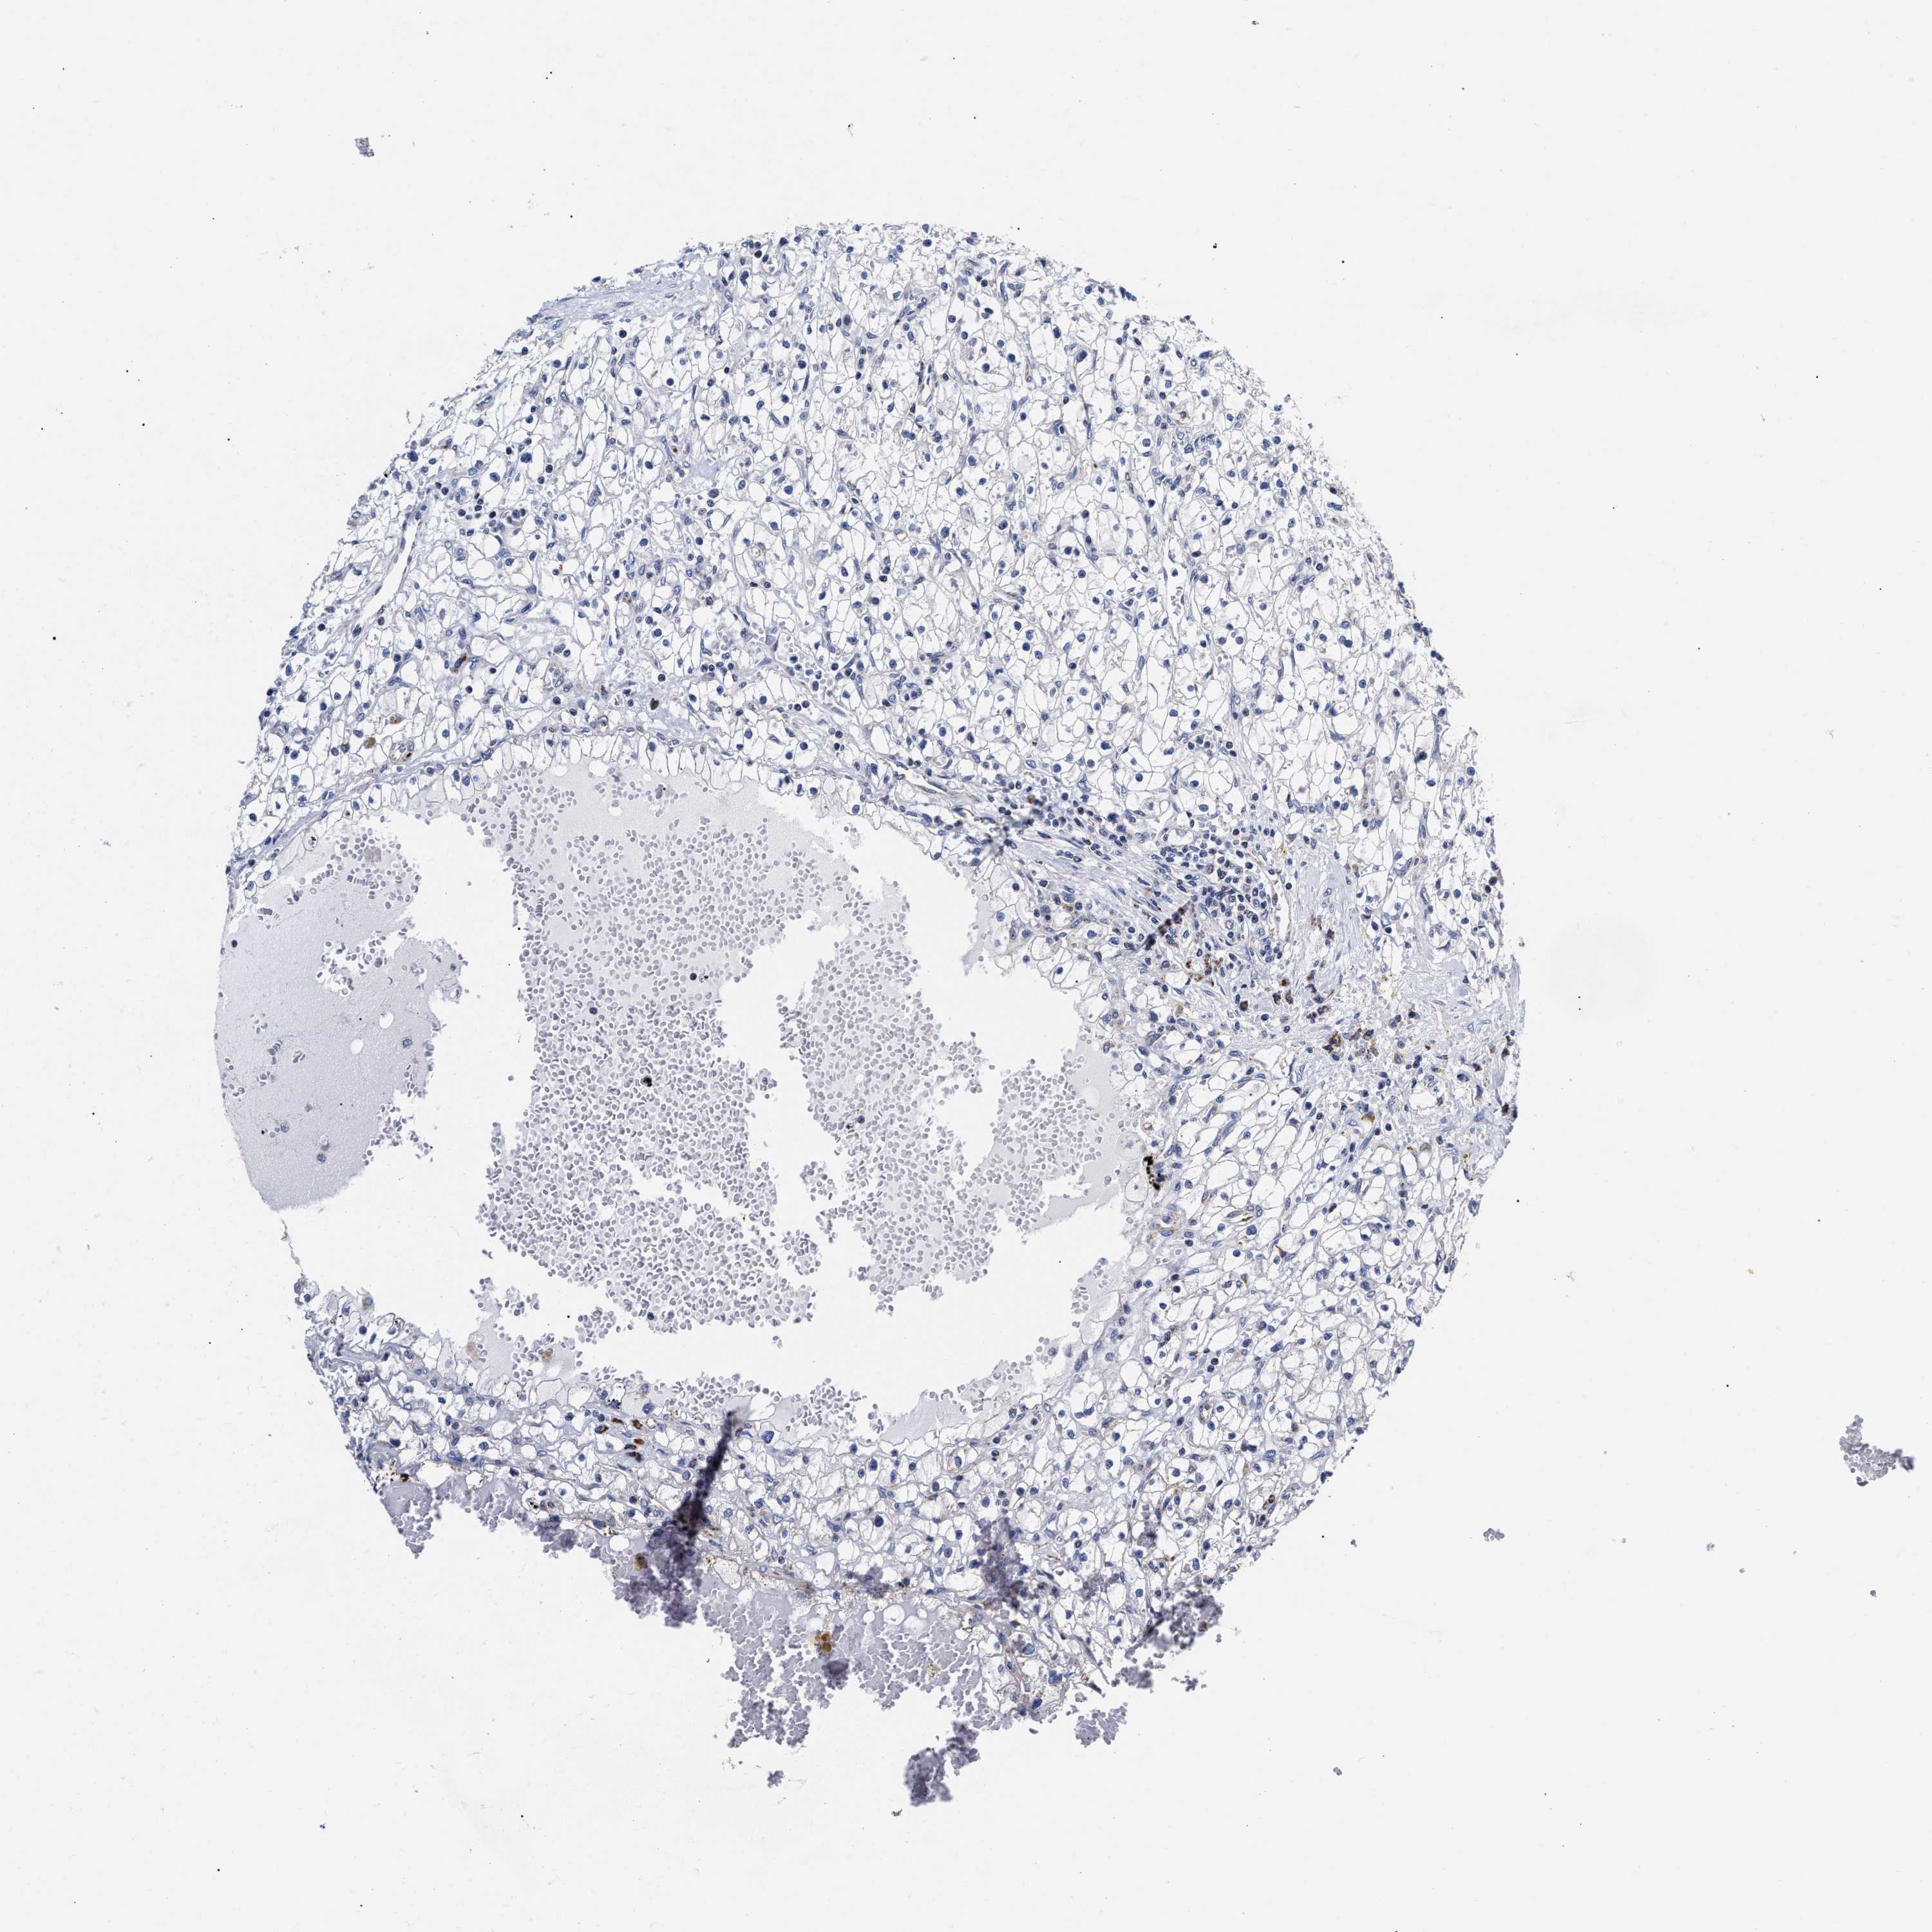

KIDNEY RENAL PAPILLARY CELL CARCINOMA (TCGA) - Interactive survival scatter ploti

The Survival Scatter plot shows the clinical status (i.e. dead or alive) for all individuals in the patient cohort, based on the same data that underlies the corresponding Kaplan-Meier plots. Patients that are alive at last time for follow-up are shown in blue and patients who have died during the study are shown in red.

The x-axis shows the expression levels (FPKM) of the investigated gene in the tumor tissue at the time of diagnosis. The y-axis shows the follow-up time after diagnosis (years). Both axes are complimented with kernel density curves demonstrating the data density over the axes. The top density plot shows the expression levels (FPKM) distribution among dead (red) and alive patients (blue). The right density plot shows the data density of the survived years of dead patients with high and low expression levels respectively, stratified using the cutoff indicated by the vertical dashed line through the Survival Scatter plot. This cutoff is automatically defined based on the FPKM cutoff that minimizes the p-score. The cutoff can be changed by dragging the vertical line or by entering a cutoff value in the square labeled "Current cut-off".

Under the Survival Scatter plot the p-score landscape (black curve; left axis) is shown together with dead median separation (red curve; right axis). Dead median separation is the difference in median mRNA expression between patients who have died with high and low expression, respectively. It is calculated as follows: median FPKM expression of dead patients with high expression - median FPKM expression of dead patients with low expression. This is intended to aid the user in visually exploring custom cutoffs and the associated p-scores and dead median separation.

Individual patient data is displayed and can be filtered by clicking on one or more of the category buttons on the top of the page. Categories describing expression level and patient information include: high, low, alive, dead, female, male and tumor stages. The scale of the x-axis can be toggled between linear and log-scale by clicking on the "x log" button. Mouse-over function shows TCGA ID, patient information and mRNA expression (FPKM) for each patient.

& Survival analysisi

Kaplan-Meier plots summarize results from analysis of correlation between mRNA expression level and patient survival. Patients were divided based on level of expression into one of the two groups "low" (under cut off) or "high" (over cut off). X-axis shows time for survival (years) and y-axis shows the probability of survival, where 1.0 corresponds to 100 percent.

HINT2 is potential prognostic, high expression is favorable in Kidney Renal Papillary Cell Carcinoma (TCGA)